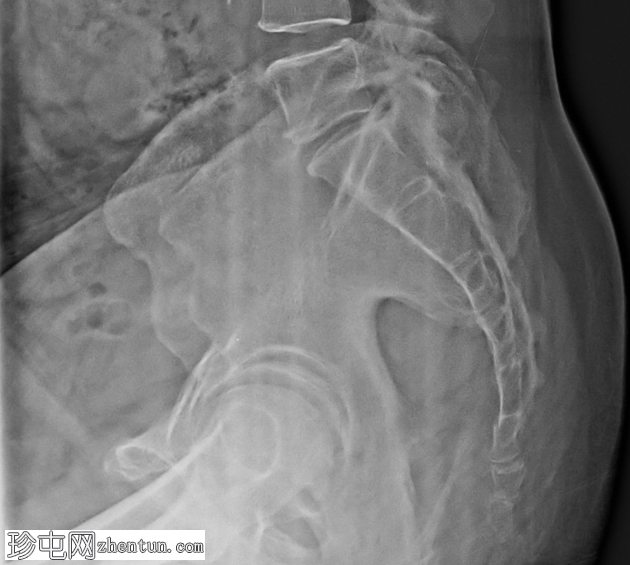

侧位X线片显示第一尾骨节段骨折线。骨折节段轻度移位。未见明显成角畸形。骶尾关节保持完整,无半脱位。其余尾骨节段排列正常。未发现骶骨骨折。

尾骨骨折最常发生于直接外伤后,例如向后跌倒,尤其是在骨密度可能降低的老年人中。侧位X线片是检测尾骨排列异常和骨折线的最有效投照方式,而正位片由于肠道气体重叠,其附加价值有限。

第一尾骨节段是最常发生骨折的部位。即使是轻微移位也可能导致剧烈

疼痛

(尾骨痛)。